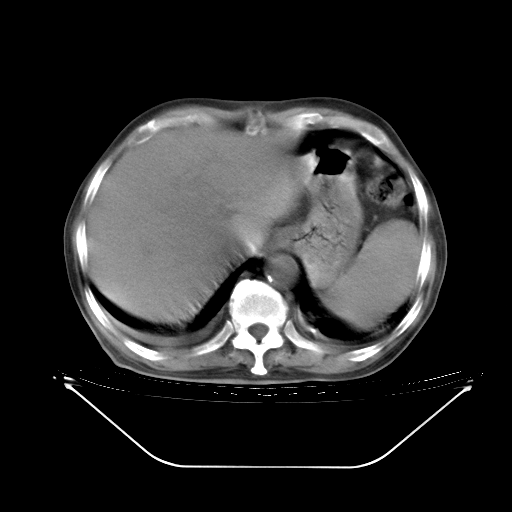

今天复查肺部CT,发现双肺广泛磨玻璃样改变。所以我把3月19日和5月9日相隔50天的肺部CT上传。请大家会诊。

2009年3月19日肺部CT片。

5月9日肺部CT(在4月27日齐鲁医院肺部CT描述部分肺组织磨玻璃样改变,12天后肺组织广泛磨玻璃样改变)